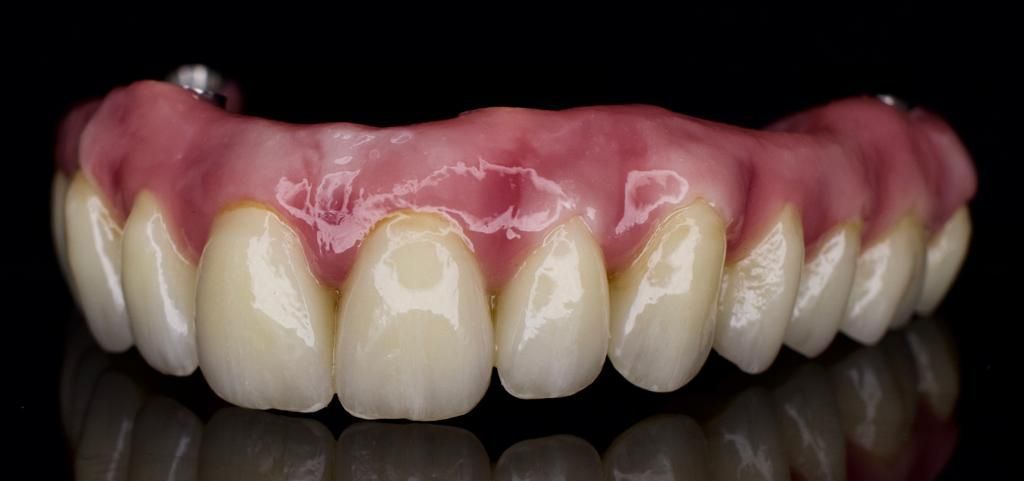

The implant retained false teeth looked and felt like real teeth, and Mike could chew and speak without any difficulty. The new teeth were also easy to clean and maintain, which was a huge relief for him.

Mike’s newfound confidence in his smile was apparent, and he found himself smiling more often than ever before. He was able to eat his favourite foods again and even enjoyed going out with friends and family without feeling self-conscious about his teeth.